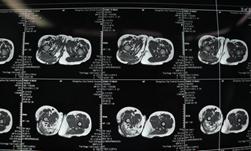

经过检查发现小诺右侧臀部及大腿有大面积的淋巴畸形,右小腿、右足踝部及右足底也有许多弥散性的肿块,不仅病变部位多且侵犯严重,加上之前已经做过三次手术,这次的手术对于医生而言无疑是巨大的挑战!经过前期充分的准备,小诺的手术如期进行,从上午10点50一直到晚上11点,历时整整12个小时,终于顺利完成手术,术中发现病变累及大面积的正常肌肉和多处神经,乔主任巧妙的采用切除和微创相结合的方式治疗病变部位,仔细分离重要的血管和神经,将大面积的病变全都切除。术后小诺身体恢复情况很好,目前正在一步步的康复,迎接她的是健康和快乐的明天!